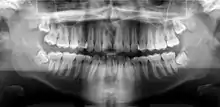

A panoramic radiograph is a panoramic scanning dental X-ray of the upper and lower jaw. It shows a two-dimensional view of a half-circle from ear to ear. Panoramic radiography is a form of focal plane tomography; thus, images of multiple planes are taken to make up the composite panoramic image, where the maxilla and mandible are in the focal trough and the structures that are superficial and deep to the trough are blurred.

![]() A dental panoramic radiograph, showing the maxilla and mandible, all the teeth including the "wisdom teeth," the frontal and maxillary sinuses, the nasal cavity and the temporomandibular joint and other near by head and neck anatomy. | |